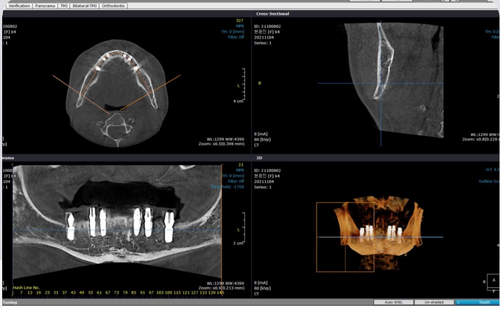

- 시설 및 장비

치과 시설과 장비도 고려해야 할 중요한 요소입니다.

현대적이고 첨단 장비를 갖춘 치과는

정밀한 진단과 치료를 제공할 수 있습니다.

최신 치과 디지털 장비를 이용하여

정확한 진단부터 지속적인 사후관리까지